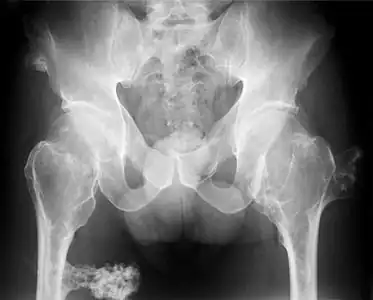

- multiple osteochondromas at the pelvis